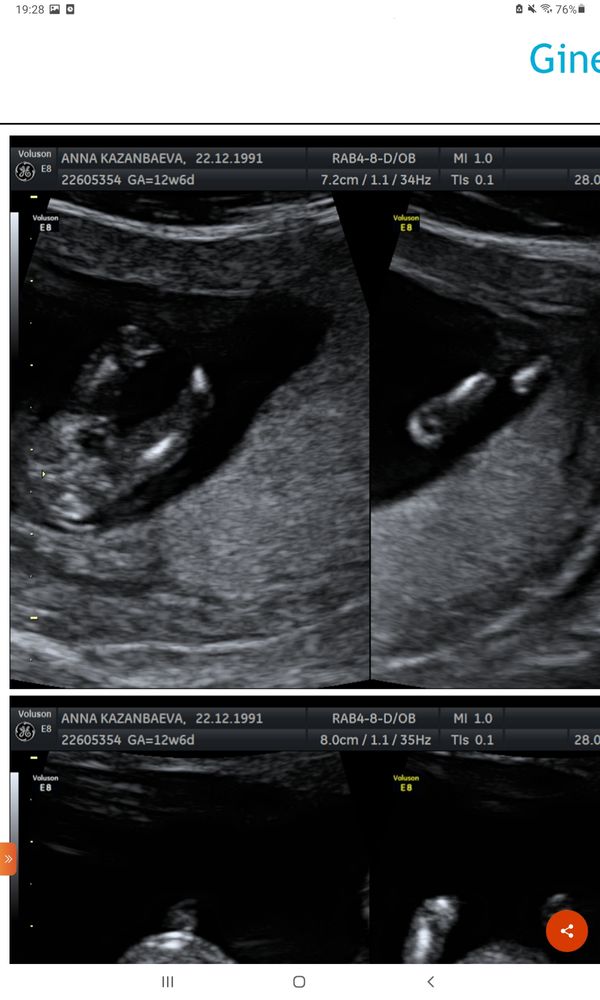

Мальчик или девочка?🙏❤🙂

Изображение На мальчика похоже. Сейчас покажу как у меня, сказали девочка...